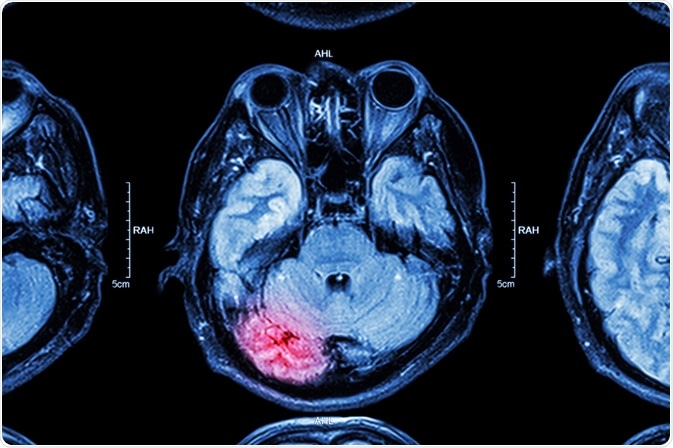

The U.S.A. alone witnesses over 50,000 deaths as a result of brain trauma. This type of sensor is likely to see widespread use, in order to pick up early signs of brain swelling, that could, if untreated, lead to irreversible brain injury, and either death or a vegetative state.

brain injuryImage Credit: Puwadol Jaturawutthichai / Shutterstock.com